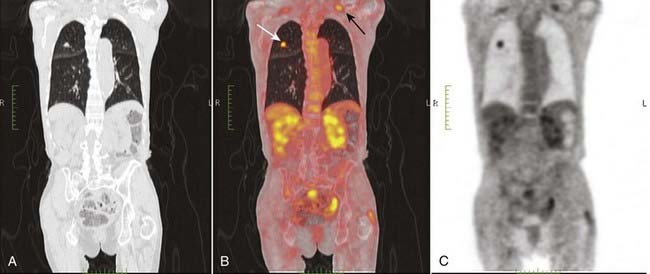

image By fusing the PET and CT images, the anatomical location of the functional abnormality is determined (Fig. 27).

image

Figure 27 PET/CT fusion image.

By fusing the PET and CT images, the anatomical location of the functional abnormality can be determined. The CT scan (A) is superimposed on the PET image (C) to form the PET/CT fusion image (B). Uptake of FDG is depicted by varying intensities of red. Normal uptake is seen in the liver (L) and normal excretion is through the kidneys (white arrows) into the bladder (B). The more concentrated the uptake, the more intense the red color.

image FDG avid lesions are those that show abnormally increased uptake of the radiopharmaceutical (Figs. 29 and 30).

Figure 29 Positive PET scan, bronchogenic carcinoma.

An FDG avid lesion is seen in the right upper lobe (white arrow) on this coronal reformatted PET/CT scan (B) confirming what was suspected to be the malignant nature of this lesion. This was an adenocarcinoma of the lung. A metastatic lymph node is seen in the left supraclavicular region (black arrow).

Figure 30 Positive PET scan, bronchogenic carcinoma with metastases.

A large right hilar mass (dotted white arrow) is FDG avid and represented a bronchogenic carcinoma (B). Less evident was a right supraclavicular lymph node metastasis (solid white arrow). PET scans are especially helpful in detecting occult metastases.